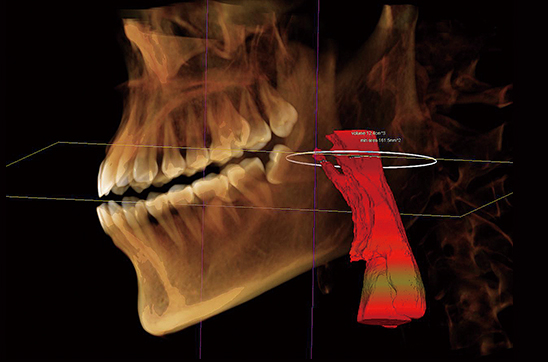

Análisis de las vías respiratorias

Proporcione datos de análisis de las vías respiratorias antes del plan de tratamiento de ortodoncia, mida el volumen de las vías respiratorias en cualquier área y determine automáticamente el área de la sección transversal de las vías respiratorias en la posición más estrecha. Especialmente para pacientes con ronquidos o SAOS, el análisis de las vías respiratorias puede ayudar a los médicos a formular el tratamiento. planes.